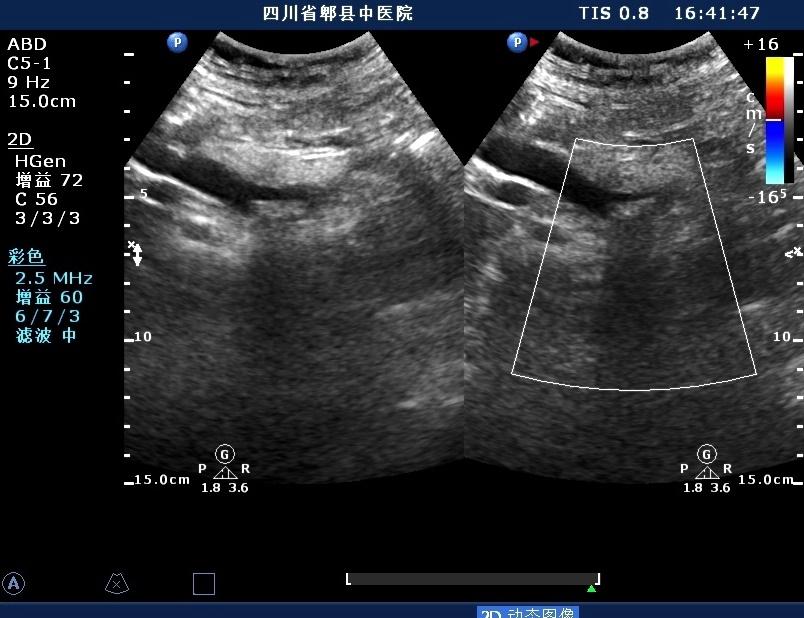

超声如图:胆总管及肝内胆管扩张,呈“平行管征”,胆总管胰腺段可见疏松强回声团堆积,后方可见淡淡声影,左肝外叶胆管内亦可见数个强回声团堆积,后方伴声影。 肝脏及胆总管

扩张的左肝内胆管

扩张的右肝内胆管